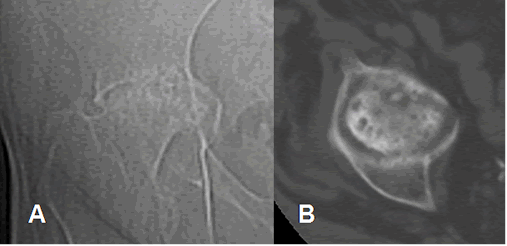

Fig 65 B. Artritis séptica residual.

A: Rx AP y B: TAC axial. Cambios residuales en la cadera, luego de una artritis séptica. Hay remodelación de la cabeza femoral y la cavidad acetabular, con pérdida del espacio, esclerosis y erosión.